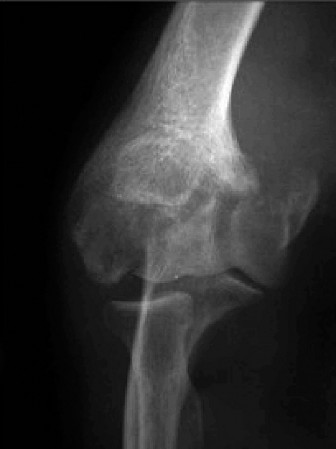

Standard Radiographs:

- Anteroposterior (AP) and Lateral Views: Essential for assessing joint space narrowing, osteophyte formation (anterior coronoid, posterior olecranon, radial head), subchondral sclerosis, loose bodies, and overall alignment.

- Oblique Views: To better visualize specific compartments.

- Capitellar View (Greenspan): Useful for assessing the capitellum and radial head.

- Stress Views: If instability is suspected (e.g., valgus stress for MCL, varus stress for LCL).

Computed Tomography (CT) Scan:

- Crucial for PTEA: Provides detailed 3D bony anatomy, excellent for delineating osteophytes, identifying and localizing loose bodies, assessing malunion of previous fractures, and evaluating bone stock, particularly for arthroplasty planning. CT with 3D reconstructions can precisely map sites of impingement and guide osteophyte resection.